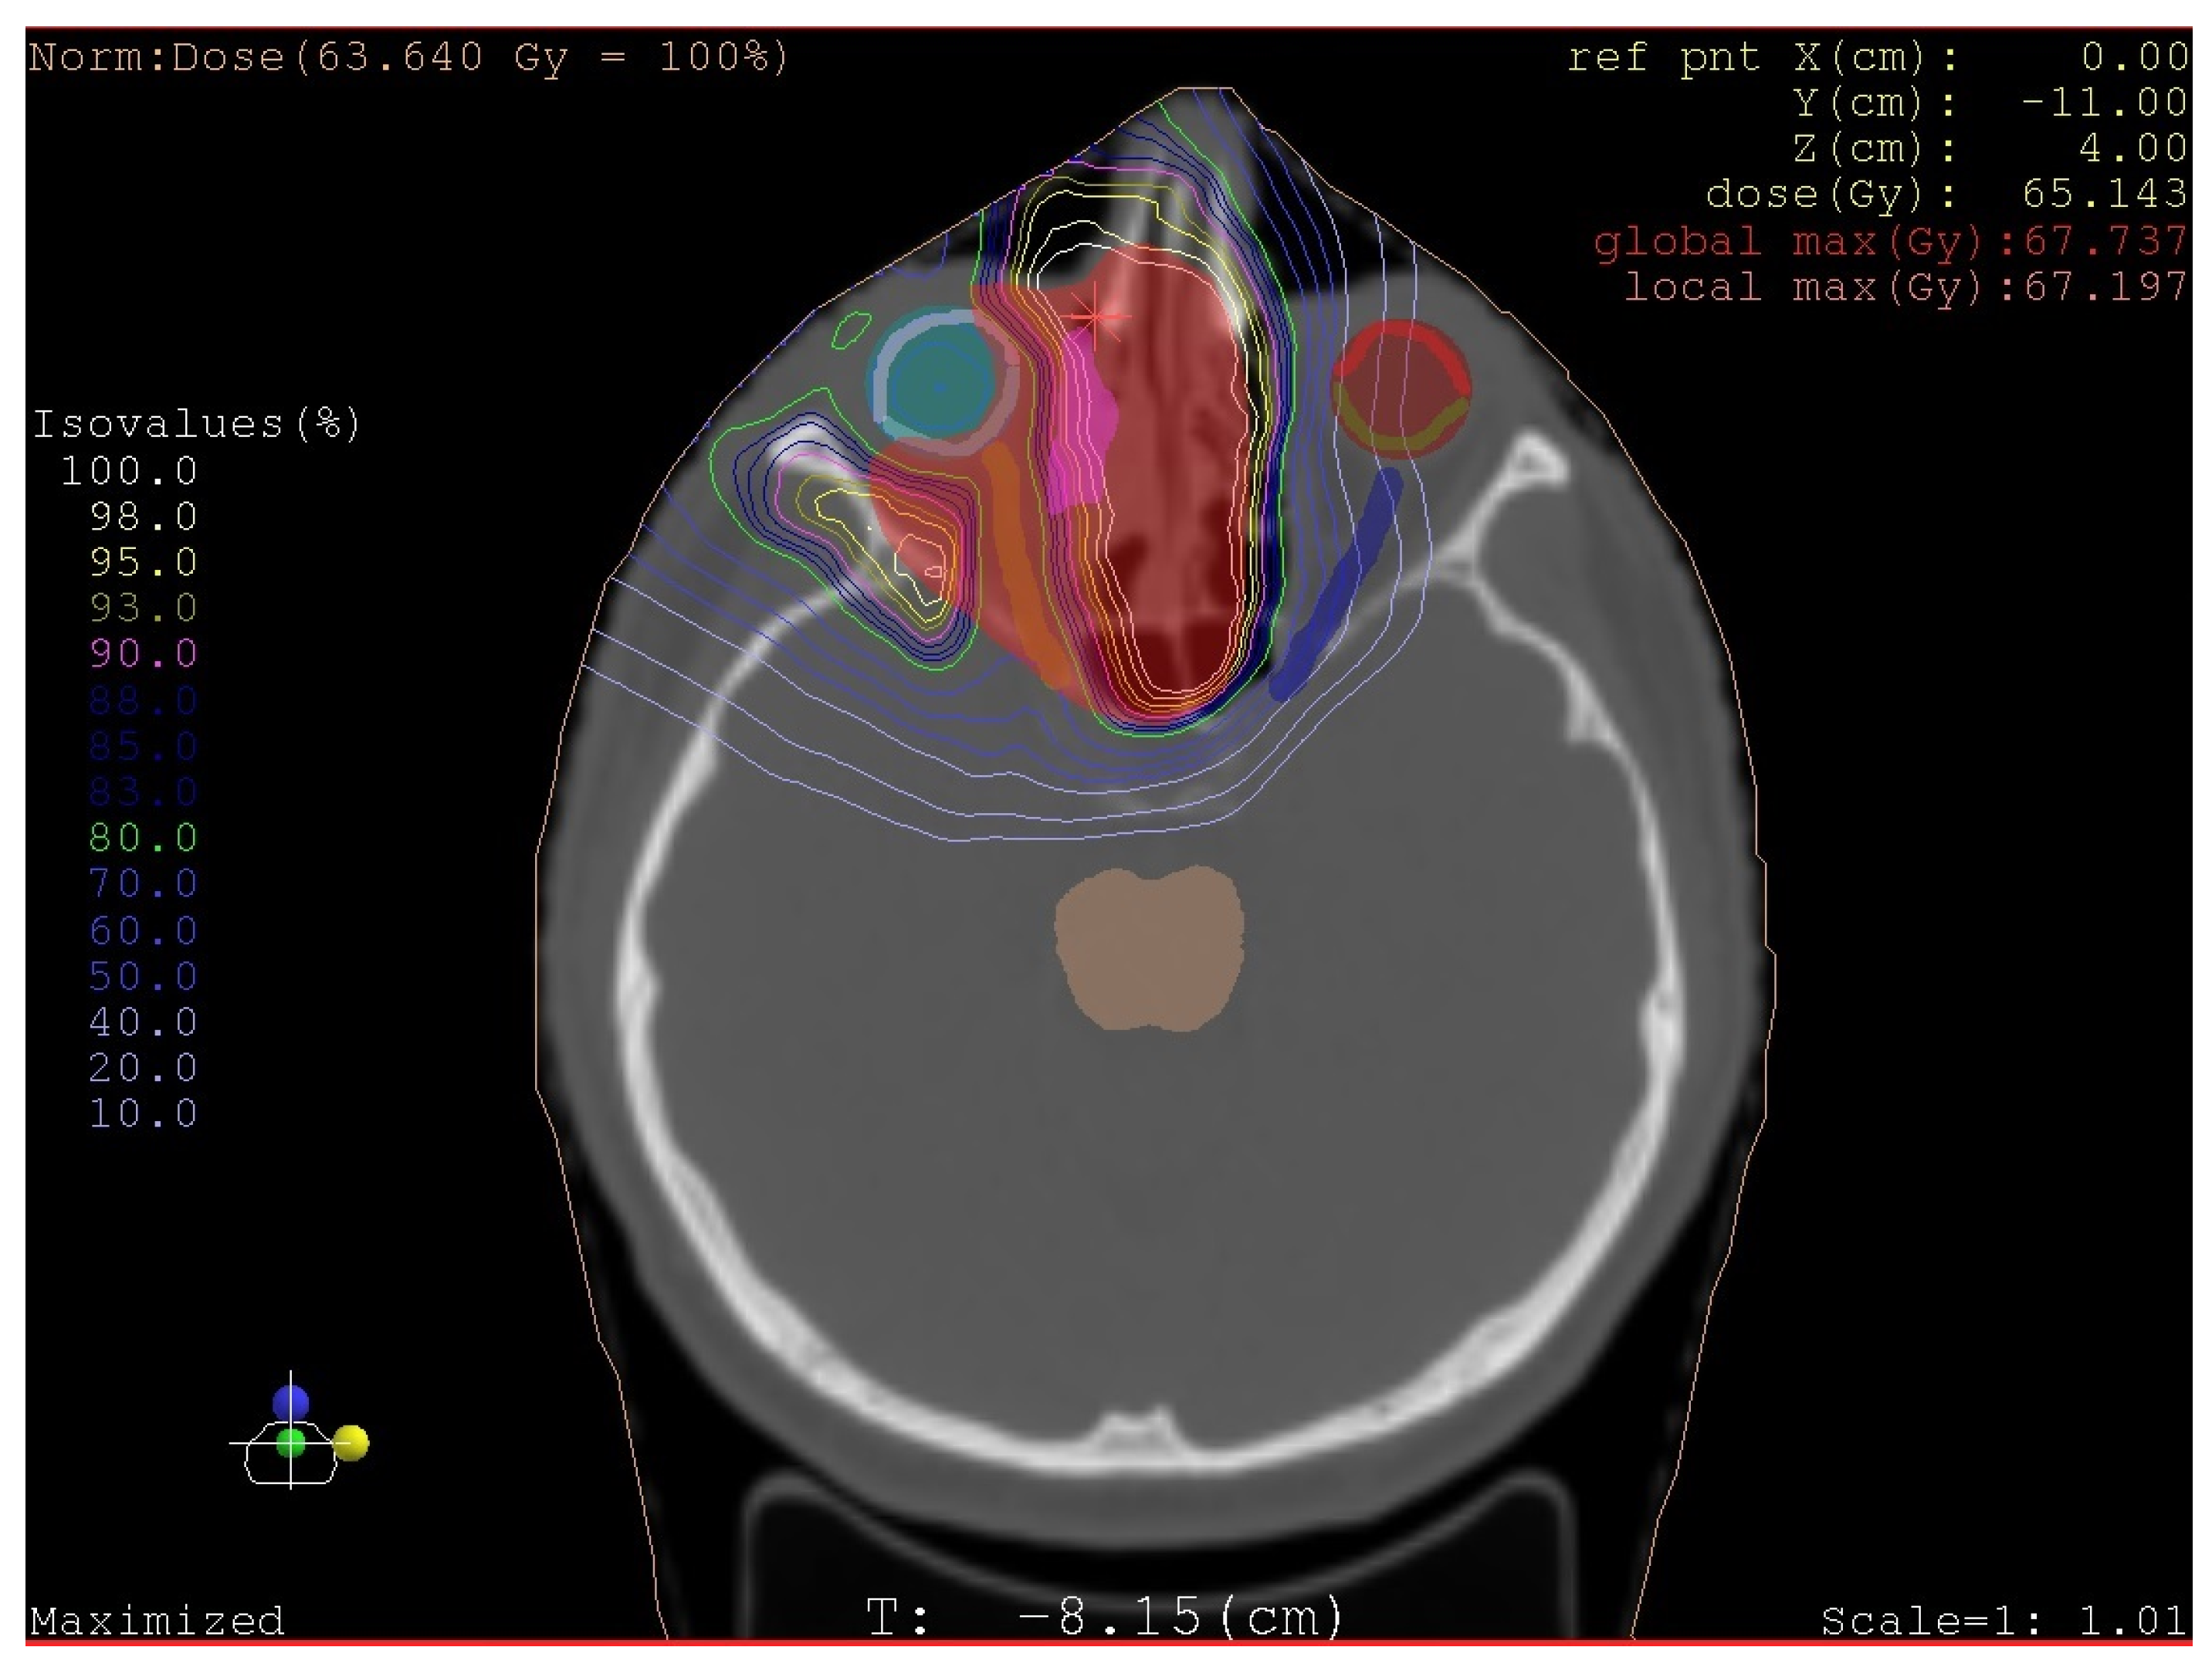

Highly Aggressive Osteosarcoma of the Ethmoids and Maxillary Sinus-A Case of Successful Surgery and Proton Beam Radiotherapy in a 65-Year-Old Man

2. Case Report (Observation)